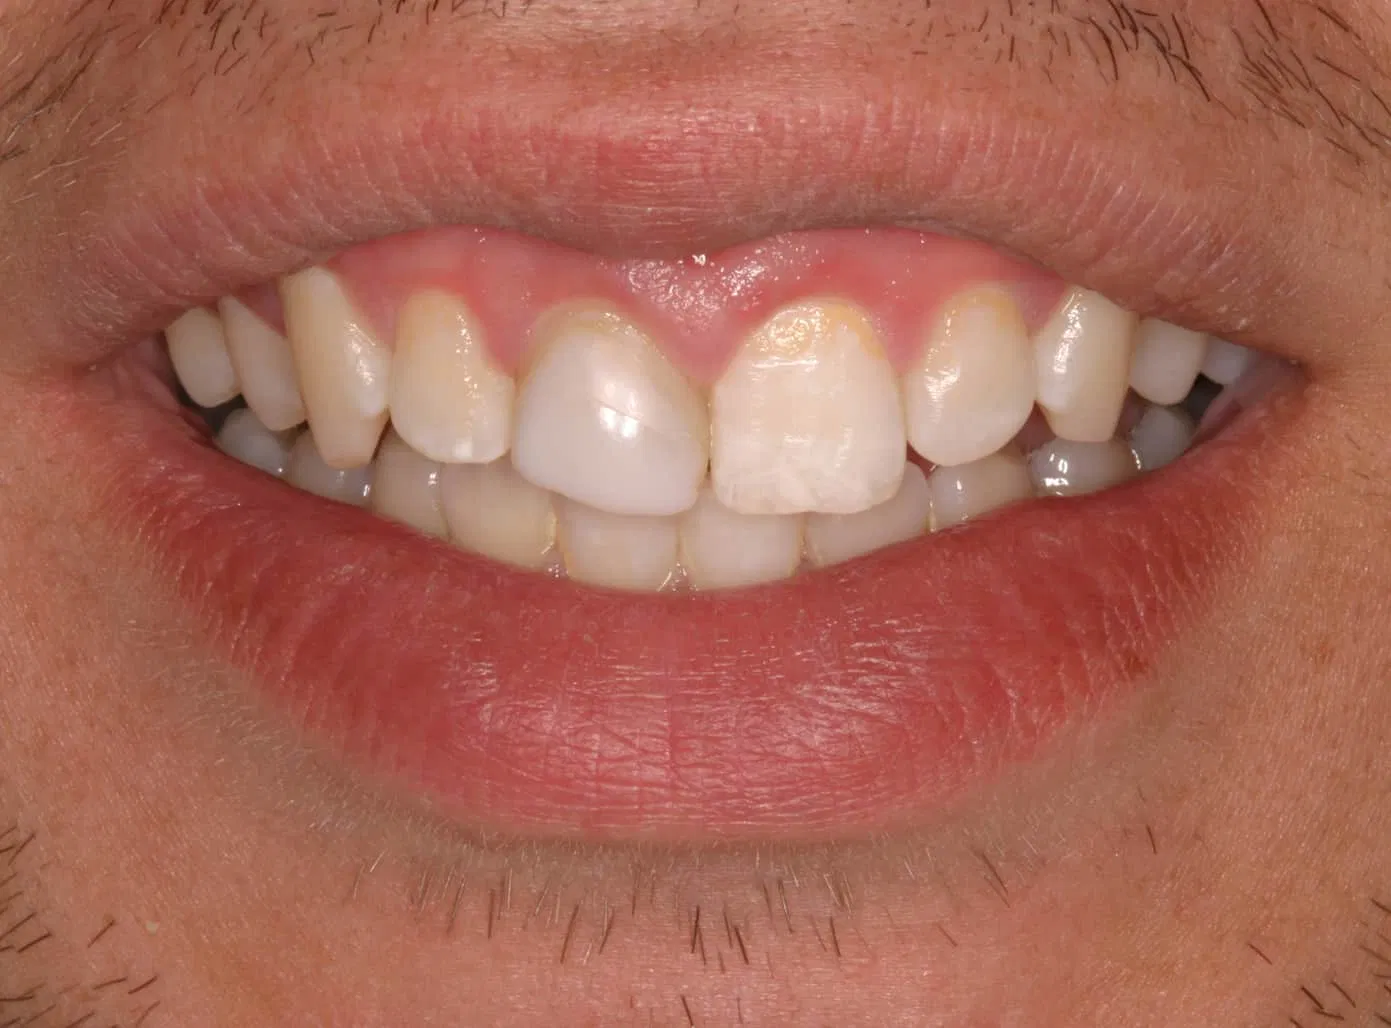

Before:Â Tooth #8 (upper right central incisor) has a history of trauma and root canal therapy. Re-treatment of the root canal filling was required.